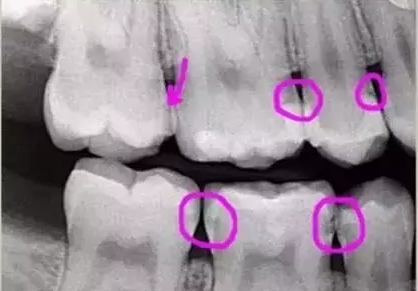

如圖躲在暗處的危險(xiǎn),如果單用肉眼是很難察覺(jué)的,通過(guò)X光片能發(fā)現(xiàn)牙齒鄰面區(qū)有多處小暗點(diǎn)(比較淺的蛀牙),而且你也沒(méi)什么感覺(jué),頂多吃飯塞牙,敏感些而已。